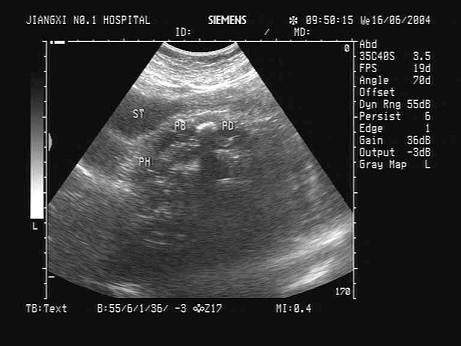

问题 患者,女,35岁,有急性胰腺炎病史,现感上腹不适。结合中上腹超声声像图表现,诊断是?(?)

选项 A.胰腺占位并胰管扩张 B.急性胰腺炎 C.慢性胰腺炎并胰管结石 D.胆总管结石 E.胰腺癌

答案 C